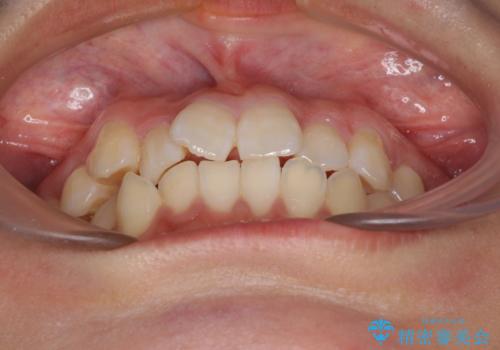

- 上下のデコボコと前歯のクロスバイトを改善したいとのことで来院された患者様です。

極力短期間で治療したいとのことで、ワイヤー装置による矯正治療を行うこととしました。